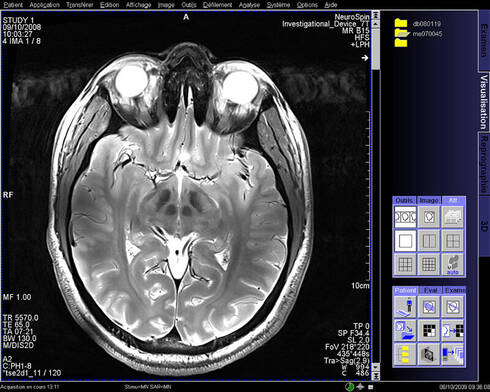

Scanner cerveau. Scanner m du cerveau liver scan échographie f du foie American English Would you like to translate a full sentence?. During the scan you will lie on a platform which slides into the scanner (a bit like going into a tunnel) It is important to lie still during the scan so that the machine can take clear pictures of your brain An MRI scan is usually a series of short scans with breaks in between, rather than one long scan. Le scanner permet par exemple de suivre l'évolution d'une hémorragie, d'une tumeur L’IRM mieux voir les organes, notamment le cerveau L' IRM (imagerie à résonance magnétique).

During the scan you will lie on a platform which slides into the scanner (a bit like going into a tunnel) It is important to lie still during the scan so that the machine can take clear pictures of your brain An MRI scan is usually a series of short scans with breaks in between, rather than one long scan. BOSTON(BUSINESS WIRE)May 4, Cerveau Technologies Inc today announced a research collaboration with University College London (UCL), a leading UK academic center for the production and application of imaging biomarkers for use in clinical research, that grants the institution the right to manufacture 18 FMK6240, a next generation investigational Positron Emission Tomography (PET. Scan (skăn) v scanned, scan·ning, scans vtr 1 a To look at carefully or thoroughly, especially in search of something;.

During the scan you will lie on a platform which slides into the scanner (a bit like going into a tunnel) It is important to lie still during the scan so that the machine can take clear pictures of your brain An MRI scan is usually a series of short scans with breaks in between, rather than one long scan. Neuromarketing scanner le cerveau un reportage de Canal Jimmy Genaro Jace Follow 6 years ago 47 views Neuromarketing scanner le cerveau un reportage de Canal Jimmy Report Browse more videos Playing next Cash investigation Neuromarketing votre cerveau les intéresse / intégrale. Et pour le coup je crois que si l'on scannait le cerveau de notre docteur en herbe, on y découvrirait de vastes zones de bêtise à l'état pur et très inquiétante pour notre système.

Un scanner cérébral est un examen d'imagerie médicale permettant d'obtenir des images en coupe de la boîte crânienne et des organes qu'elles renferment cerveau, nerfs optiques, nerfs. En fait, pour scanners réalisés avant l'âge de 10 ans, on risque de voir se développer un cas de leucémie et un cas de tumeur cérébrale dus aux rayonnements dans les dix années. 14 juil 19 Découvrez le tableau "Cerveau" de Stephanie Hernandez sur Voir plus d'idées sur le thème cerveau, neurosciences, le cerveau.

Submit a new entry Compile a new entry powered by Free PONS Apps Our free PONS Online Dictionary is also available for iOS and Android!. Cerveau Technologies Inc signed an agreement with the MGH Gordon Center to support multiple projects over the next several years These research projects are for studies of an early stage imaging agent (MK6240) to be used in Positron Emission Tomography (PET) scans for assessing the status and progression of neurofibrillary tangles (NFTs) in the brain. Le scanner cérébral, ou tomodensitométrie cérébrale, est un examen utilisant les rayons qui permet de visualiser de cerveau et d’éventuelles anomalies.

Le scanner a également révélé que le volume des zones ischémiques était supérieur de 47 % à l'échelle du cerveau chez ces mêmes sujets par rapport au reste de la population étudiée, et. Pour un scanner cérébral, le patient est allongé, en général sur le dos, sur un lit qui se déplace automatiquement dans un large anneau Il doit garder les deux bras sont allongés le long du corps et sa tête est immobilisée par une fixation dédiée. In addition to ultrasounds, another scan commonly used in standard cancer diagnosis is a CT scan CT stands for Computed Tomography It's an imaging tool that uses Xray technology to produce scans of the inside of the body.